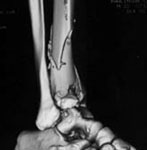

From: chris wilson

Thank you all for your interest. A lot of list members are telling me to fix the fibula and raise and graft the tibial plafond. I enclose 2 other small images to convince you that the fibula is intact and the tibial metaphsis has been well reduced, and in these circumstances is there any thing we can do about the talar tilt and to improve the prospects of avoiding post-traumatic OA?

Regarding case of distal tibia fracture treated with reduction and multiple screw fixation supplemented by a small wire external fixator. The talus is tilted in the mortice and the question is what, if anything, to do.

I suggest trying to determine why the talus is tilted. Does it reduce with inversion stress? (appears less tilted on the last xray in second message). If it does not, what is blocking it? Could the posterior tibialis tendon or something else be interposed. If so, can it be removed? Is the distal tibia medial fragment malrotated causing the appearance of talus tile? This looks like it might be true on the first CT and plain xray where the talus seems more normally positioned relative to the fibula. If so, could the medial side of the ring be lengthened or could this fragment be manipulated and re-fixed? What is the talus fracture? Is it the lateral edge of the dome or something else? I would try to get the talus better positioned in the mortice, although I do not think it is crucial to determining outcome. Perhaps a splint in inversion or add hindfoot pins to the fixator and make this a spanning XF or perhaps one of the etiologies mentioned above could be identified and corrected.